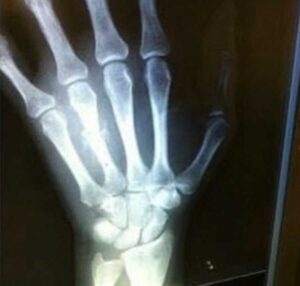

My wedding finger was ‘ruined’ back in 2011. I was in a very abusive relationship and one of the worst things my abuser did to me was stab me through my hand, breaking the bone of my left ring finger.

When my abuser stabbed me, he did it with such force that the blade completely broke off the knife. The doctors did some X-rays, and it was decided that I was going to need surgery. Once I got out of the X-Ray, I realized my abuser had left me in the hospital alone. I called his mom to let her know the truth about what happened and I was met with gaslighting. She told me, ‘This is your fault because you made him too angry.’ After I heard that I felt so alone, but thankfully I did not have to worry about my son because my mom was taking care of him.